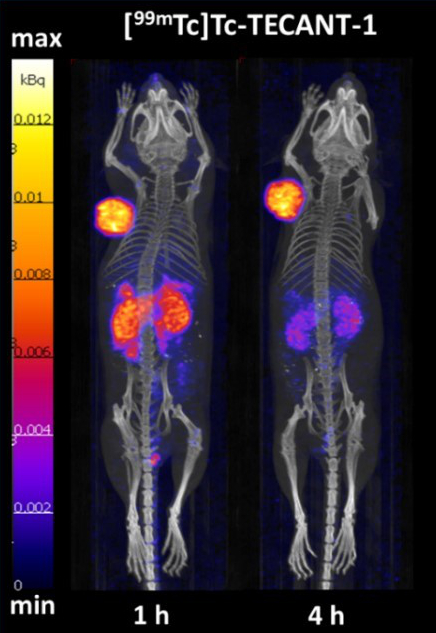

The overexpression of somatostatin receptors (SSTR) predominantly of subtype – 2 (SSTR2) in neuroendocrine neoplasms is an established target for radiopharmaceuticals, which allows prediction and evaluation of response to various available therapies. The development of a receptor antagonist labelled with technetium-99m for SPECT with superior imaging properties is the aim of the ERA-PerMED project “TECANT” [https://www.era-learn.eu/network-information/networks/era-permed/1st-joint-transnational-call-for-proposals-2018/] supported by FWF (proj. no. I 4220-B). SSTR antagonists were prepared and compared preclinically in respect of their pharmacological properties in vitro and in vivo to provide a basis for clinical translation. [99mTc]-TECANT 1, which has higher tumour uptake and retention, was selected. Fig. 6 shows a micro-PET study in tumour-bearing mice displaying excellent targeting of [99mTc]-TECANT 1, from [13]. Radiation dose estimates predict a low acceptable radiation dose for patients. The project is a collaboration between universities in Krakow in Poland, Ljubljana in Slovenia and Basel in Switzerland. The clinical trial will begin in 2021.